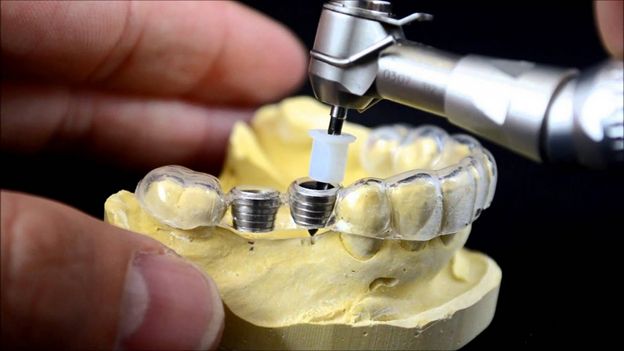

- دوام ایمپلنت؛ یکی دیگر از مسائل حائز اهمیتی که در مبحث تاثیرات ایمپلنت توسط بهترین کلینیک کاشت ایمپلنت تهران مطرح میشود، دوام دندان کاشته شده میباشد. دندانهای ایمپلنت شده از دو قسمت کلی پایه تیتانیومی و روکش ایمپلنت تشکیل یافتهاند که کیفیت پایین هر کدام ممکن است ظرف مدت زمان کوتاهی منجر به از دست دادن دندان ایمپلنت شده، شود. از آنجایی که مراکز معتبر و تخصصی در تهیهی این ایمپلنتها دقت و اهتمام بیشتری به کار میبرند، معمولا ایمپلنت انجام شده از دوام بالایی برخوردار بوده و در موارد بسیاری مادامالعمر خواهد بود.

مواد مورد استفاده در ایمپلنت

یکی دیگر از مواردی که تعیین کننده بهترین کلینیک ایمپلنت تهران است، کیفیت مواد مورد استفاده در ساخت روکش ایمپلنت و دیگر اجزای آن و برند ایمپلنت مورد استفاده میباشد. چرا که استفاده از بهترین برند ایمپلنت در جوش خوردن آن پیچ در لثه و دوام ایمپلنت بسیارتاثیرگذار خواهد بود. همچنین کیفیت بالای مواد مورد استفاده کمک میکند تا فرد بتواند همانند دندان طبیعی با آن رفتار کرده و حساسیت بالایی در برخورد با آن نشان ندهد.